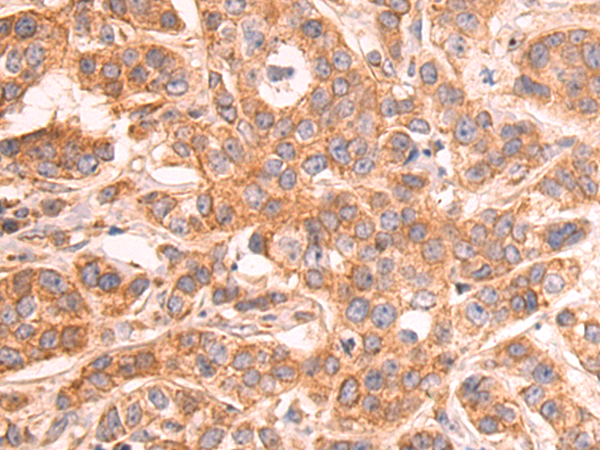

分类: 科研抗体货号: P08417别名: C11; CDR; DD4; CHDR; DD-4; HAKRA; 3-alpha-HSD应用: WB,IHC反应种属: Human